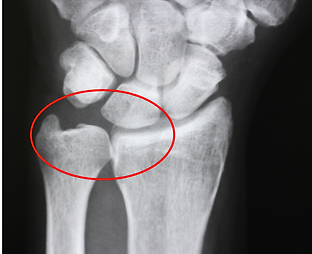

手関節の中央にある月状骨が壊れる病気です。大工さん等の手をたくさん使う人に発症しやすいといわれております